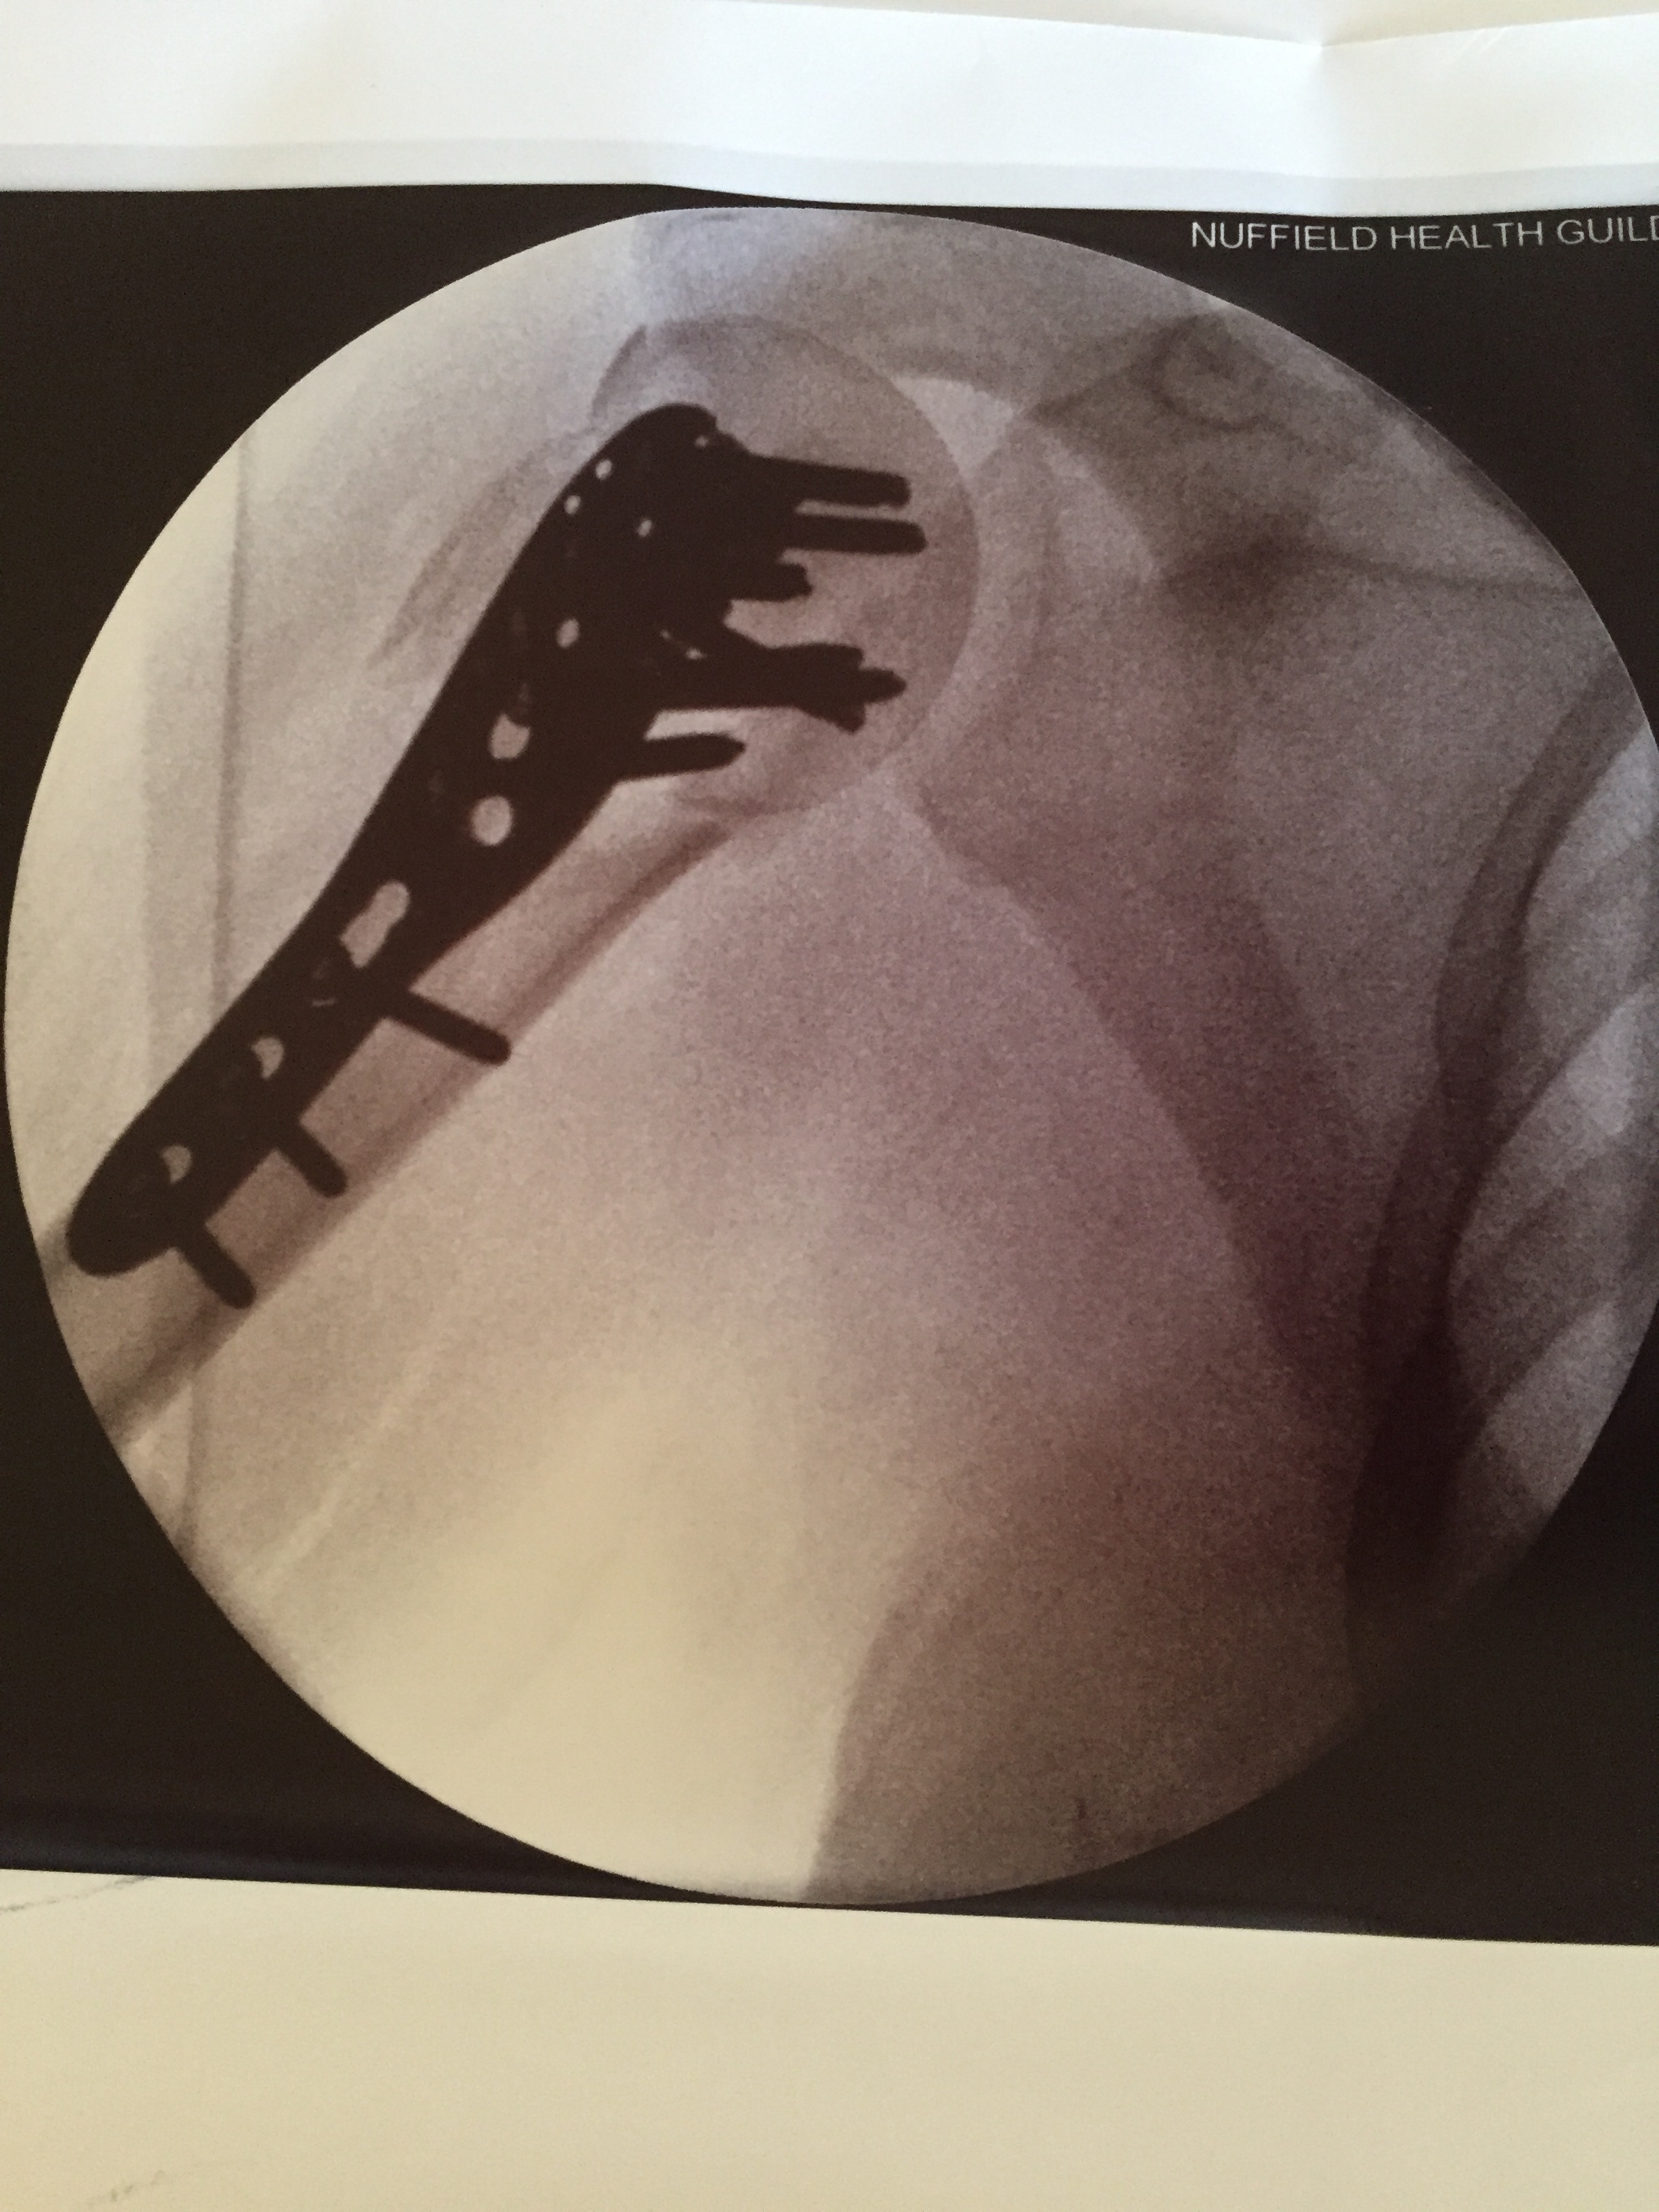

The outpatients appointment was depressing. I can’t explain how important these milestones are ~ you count the days to them. I am at home alone all day literally counting down to the next outpatients. Today I had an x ray, saw the Lovely Mr F and had physio.

The guy in x-ray told me that Mr F had asked him to help during the operation because he was unsure how it was going to go it was such a severe injury. As it happened he couldn’t help as his wife, in his words, ‘inconveniently gave birth’! I have very little movement in my shoulder and he told me it’s 12 months rehabilitation.

Four months until I can ride a bike or go swimming and at least six months before I can contemplate getting on a horse. The Lovely Mr F. has signed me off sick completely for another month. He said that physically and psychologically I have no capacity to work yet as I was assaulted twice; once on the slopes and once by him. He said I will feel tired ratty emotional and he was exactly right. I cried in the hospital, I cried when I got home. I saw the physio and she very gently moved my arm for about 15 minutes to try and get some movement into it. It is very stiff and I have to return next week. Following the physio the pain got worse. I think the worst of it is that he said I have to have another operation later this year to remove the pins.